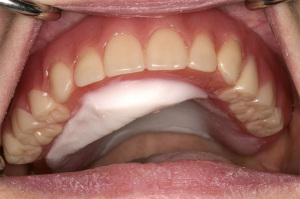

Palatal augmentation prostheses

Palatal drop or palatal augmentation prosthesis provides a reshaped palatal surface to improve tongue/palate contact during speech and swallowing (27) improving speech and swallowing (41,42). The tongue is an important articulation organ. It moves rapidly between different articulatory positions and tongue-to-palate contact is important for plosive consonant, e.g., /t/ and /d/. The shape of oral and pharyngeal cavity is also formed by the tongue during production of different vowel sounds. For this reason, some patients use a palatal augmentation prosthesis can to help to pronounce more precisely especially for velar sounds (41).

A palatal augmentation prosthesis consists of an acrylic plate covering the hard palate with retention derived from clasping of the teeth. The shaping of the augmentation of the palatal vault is made using functional impression against the tongue during function (Figure 4). This intraoral device can help not only patients with tongue impairment, but also patients with decreased glossal muscle strength (43). Therefore, this type of prosthesis is often used after glossectomy (42) and other oncologic surgeries with oropharyngeal neurological and motor sequelae (44) and stroke victims (43,45).

Bolus transformation and transfer to the pharynx is enabled by the tongue since the pharyngeal squeezing pressure is generated by tongue pressure. Pharyngeal transit time can be reduced when contact between the tongue and palatal region is facilitated by using palatal augmentation prostheses (43).

Different materials and designs have been employed to improve palatal augmentation prostheses. Removable thermoplastic sheet material for the palatal vault component can be used to reduce weight and facilitate prosthesis hygiene compared to the use of acrylic resin (46).